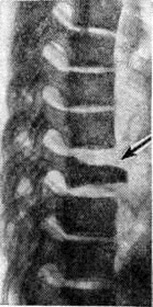

Остеохондропатия тела позвонка развивается в результате нарушения его кровоснабжения, причины которого не ясны. Поражается один позвонок в нижнегрудном или верхнепоясничном отделах позвоночника. Первым и основным симптомом является постепенно нарастающая боль в области поражённого позвонка. При пальпации позвоночника отмечается локальная болезненность, ограниченное напряжение мышц и небольшое выступание остистого отростка поражённого позвонка. Общая или местная температурная реакция и изменения в гемограмме отсутствуют. Рентгенологическое симптомокомплекс — платибрахиспондилия, то есть уплощение тела позвонка и его расширение. Высота тела позвонка снижается как в переднем, так и в заднем отделах, и он приобретает вид узкой полоски, выступающей кпереди на несколько миллиметров (рисунок). Межпозвонковые диски в этом участке расширены.